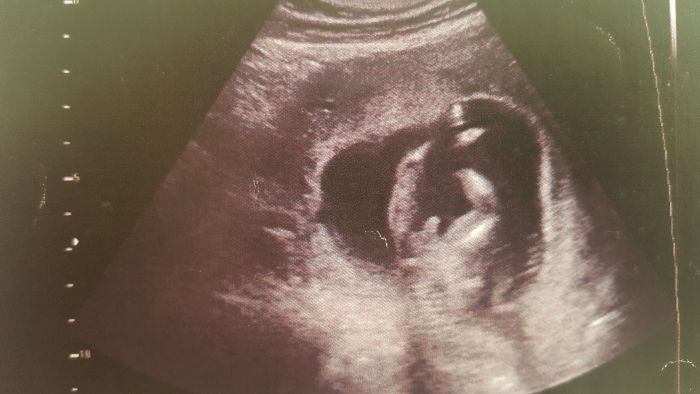

[883505]joo tak tady uz ho vidiiim

[883510] dnes 13+1

ale tohle video mám z 31.3.

Simčo. Já čekám kluka už po několikáté a já vidím to, co u nás. Kluka.

Siimo, tohle je utz ze13 tydne z minuleho tehu a ted kdyz jsme byli na utz take ve 13 tydnu tak to bylo videt stejne jen byl otoceny zadeckem

[883546]ty jo tak tam je fakt pinda, ale u nas je to asi fakt jeste nejiste,doktor rikal ze z toho fakt muze byt jeste kacka, ale mi je to jedno, budu rada za oboji :-) i kdyz pritel by samozrejme radsi chlapecka

Kdyz oni to maji v tomhle tydnu vazne skoro stejny, z te tve fotky bych si nebyla jista. Kdyz to vylozene na tebe nekrici... :) az kolem toho 20 tydne ti to muzou rict s vetsi presnosti. U nás se teda ani jednou nespletli ale v porodnici se mnou byla mamina ktere rikali dva doktori ze kluk a narodila se holcicka.